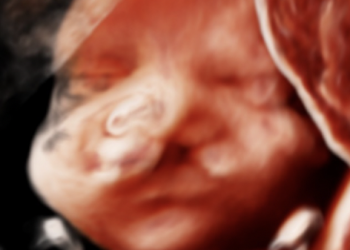

Per il mese di Gennaio SIEOG Giovani presenta il Webinar sullo studio 2D e 3D del viso fetale. Per...